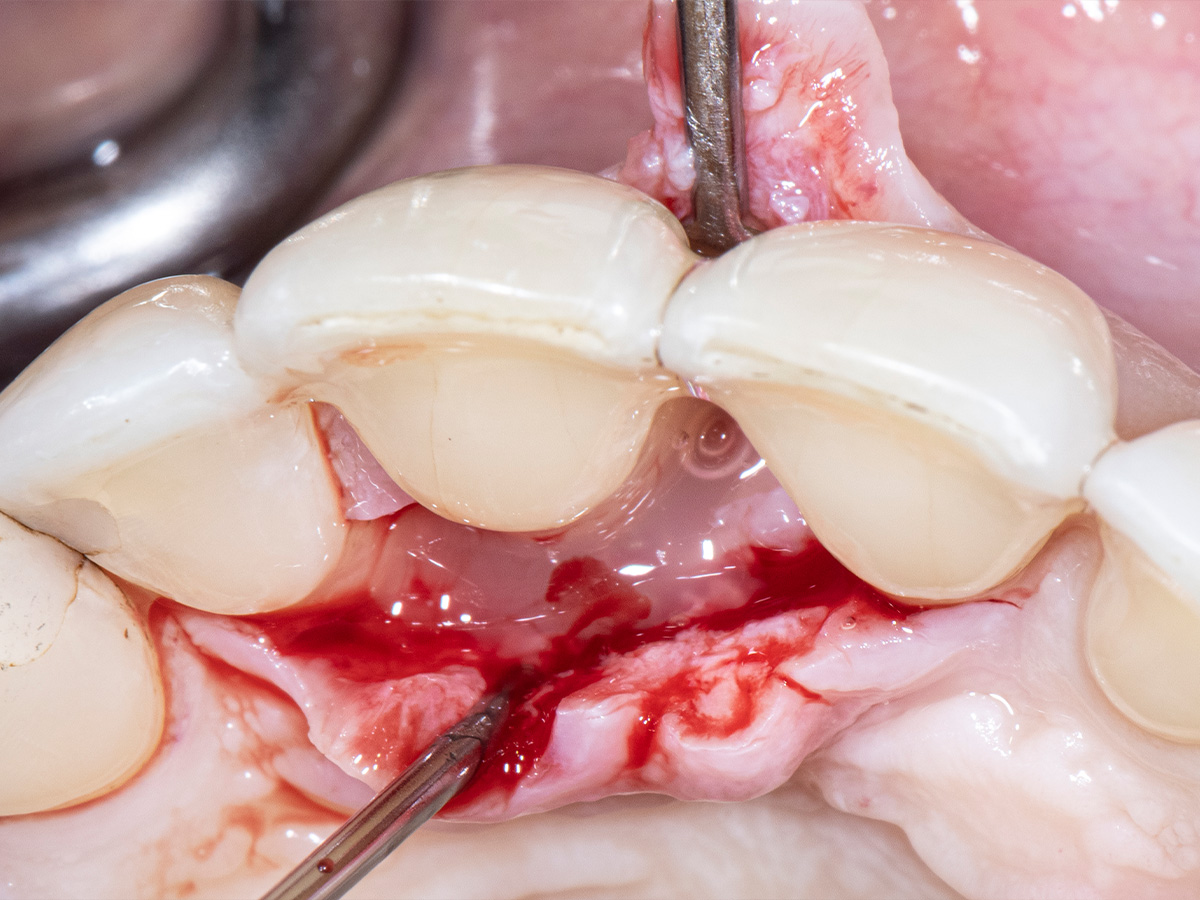

Um den mesiobukkalen Aspekt des Defekts zu erreichen, wurde ein zweiter Lappen mit einer ultradünnen und biegbaren Keydent Spin Blade 360 präpariert, die an die jeweilige anatomische Situation angepasst werden kann und präzise intrasulkuläre Inzisionen im Interproximalraum sowie ein vorsichtiges Abtrennen des entzündlichen Infiltrats vom Weichgewebe und ein anschließendes sanftes Herauslösen auf die bukkale Seite ermöglicht.

Abbildung 6

Abbildung 7

Nach gründlicher Reinigung...

Abbildung 8

wurden autogene Knochenspäne sowie Schmelzmatrixproteine appliziert...

Abbildung 9

und die Lappenenden mit Nähten spannungsfrei adaptiert, um eine Heilung per primam zu ermöglichen.